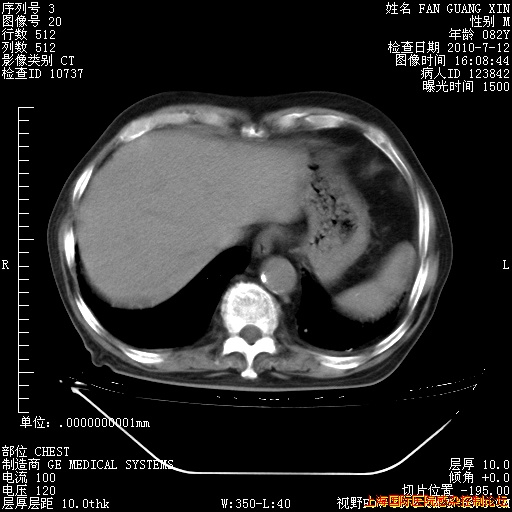

今天复查CT

今天CT

整整相隔30天的肺部CT好像有所好转啊。甲强龙减量第3天,需要观察体温。

海管,自昨日你和我通完话后,不知您岳父消化道症状有无缓解?体温怎样?阅读7.12日胸部ct,个人认为目前激素治疗是有效的,甲强龙减量是适宜的。因在抗痨治疗,需密切观察肝功、肾功能和血常规。不过,老年、长期住院和大量使用激素,很担心菌群失调发生